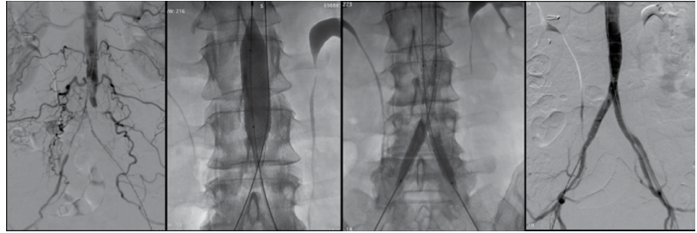

Observe as imagens:

(Arquivo pessoal; imagem usada com autorização)

Assinale a alternativa que corresponde à técnica operatória apresentada nas imag

A

EVAR.

B

NAISS (

New aorto-iliac stent system

).

C

COBEST.

D

CERAB.

E

SAFARI.